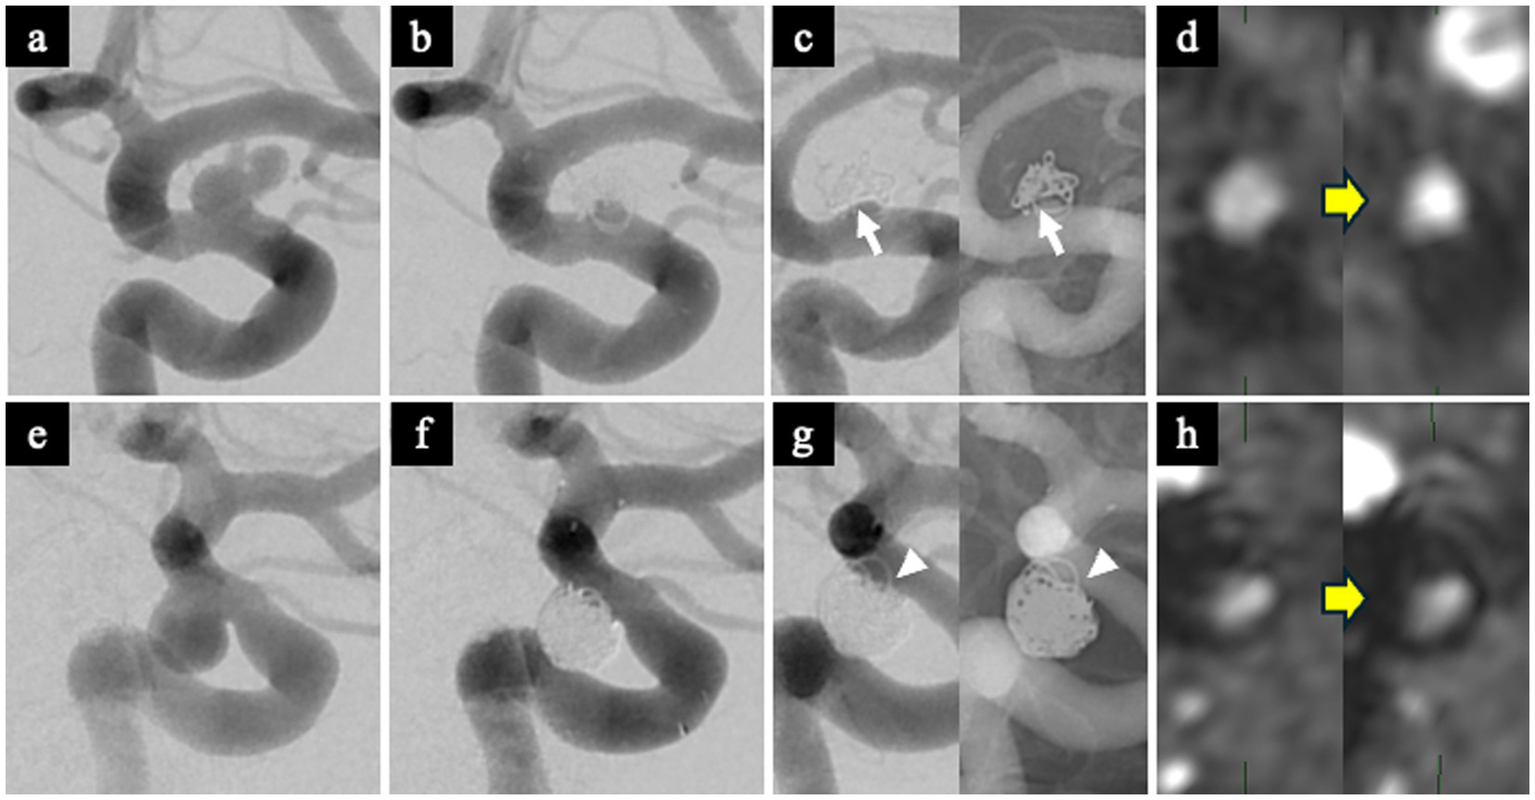

Representative cases

WCS-positive case

A 62-year-old man with a left ICA aneurysm (neck size: 4 mm) underwent SAC. The RROC classification immediately after treatment was Class 2, with a VER of 12.1% (Figures 5a,b). Follow-up DSA at 1 year clearly showed the WCS (Figure 5c). TOF-MRA showed an increase in TOF-SIR from 0.39 on postoperative day 1 to 0.60 at 1 year, corresponding to a change of 0.21 (Figure 5d).

Figure 5

Representative WCS-positive and WCS-negative cases. WCS-positive case (a–d). (a) Preoperative DSA showing a left ICA aneurysm. (b) Immediate post-embolization DSA demonstrating Raymond-Roy Occlusion Classification (RROC) Class 2 occlusion. (c) Follow-up DSA at 1 year showing a clear WCS at the aneurysm neck (white arrow). (d) Postoperative TOF-MRA showing increased TOF-SIR at 1 year compared with postoperative day 1, indicating improved vessel visualization. WCS-negative case (e–h). (e) Preoperative DSA showing a left ICA aneurysm. (f) Immediate post-embolization DSA demonstrating RROC Class 2 occlusion. (g) Follow-up DSA at 1 year showing no evidence of the WCS (white arrowhead). (h) Postoperative TOF-MRA showing minimal change in TOF-SIR between postoperative day 1 and 1 year. RROC, Raymond-Roy Occlusion Classification; TOF-MRA, time-of-flight magnetic resonance angiography; TOF-SIR, time-of-flight signal intensity ratio; WCS, white-collar sign.

WCS-negative case

A 38-year-old woman with a left ICA aneurysm (neck size: 4.6 mm) underwent SAC. The RROC classification was Class 2, and VER was 33.6% (Figures 5e,f). Follow-up DSA at 1 year did not demonstrate the WCS (Figure 5g). TOF-SIR showed minimal change, increasing from 0.29 on postoperative day 1 to 0.31 at 1 year, a change of only 0.02 (Figure 5h).